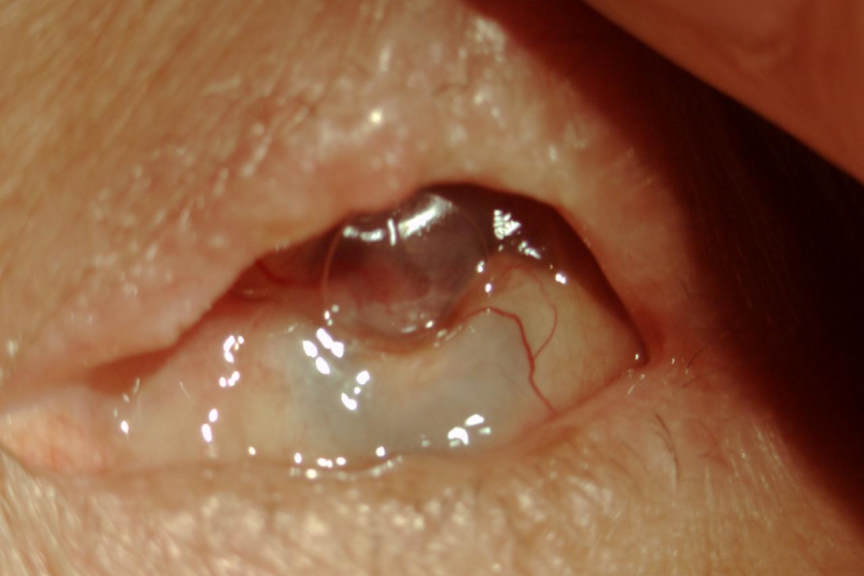

Case study: There was an old lady who fly sprayed her eye…

A peculiar case of corneal oedema in an elderly patient, highlighting the importance of obtaining collateral history when there’s no obvious cause.